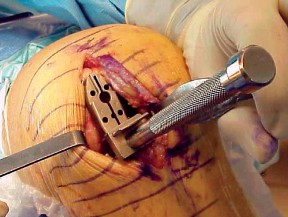

2. الوضع الجراحي والتعرض

- الوضع: يُوضع المريض في وضع الاستلقاء (Supine positioning) مع وضع كيس رمل أسفل الركبة أو حامل للساق يسمح بثني وفرد الركبة. يجب أن يكون الوضع مماثلاً لوضع جراحة TKA، مع استعداد لتحويل الإجراء إلى TKA إذا لزم الأمر.

- العاصبة (Tourniquet): تُستخدم عاصبة وتُوضع في أعلى الفخذ لتقليل النزيف.

-

الشق الجراحي:

يُستخدم شق طولي في الجانب الإنسي (الداخلي) من الركبة. يجب أن يكون الشق كبيرًا بما يكفي لتوفير رؤية جيدة للمفصل الرضفي الفخذي وإمكانية التحويل إلى TKA.

- فتح المفصل (Arthrotomy): يكون الفتح خطيًا وموازياً لألياف الوتر الرضفي، ويمتد إلى عظم الظنبوب وإلى الجزء السفلي من الرضفة.

- تحرير الأنسجة الرخوة: يتم قطع الغضروف الهلالي لتحرير الأنسجة الرخوة من عظم الظنبوب، ويتم تطوير سديلة تحت السمحاق في نمط دائري حول الظنبوب. يُمدد هذا التحرير خلفيًا لضمان توازن الأربطة.

-

تصحيح التشوه:

الهدف هو تحقيق تصحيح طفيف للتشوه، مع وجود رخاوة كاذبة طفيفة عند تطبيق ضغط تفحجي في نهاية الإجراء. يجب تجنب التصحيح المفرط.